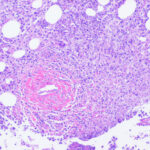

The histopathologic picture in nontuberculosis mycobacterioses is just as variable as the clinical picture and may present nonspecific acute and chronic inflammation, suppuration and abscess formation, or tuberculoid granulomas with or without caseation . In some instances, both tissue reactions occur concurrently. The presence or absence of acid-fast bacilli depends on the tissue reaction. In suppurative lesions, numerous acidfast bacilli often can be found. |

Infection with Mycobacterium Kansasii M. kansasii is usually a lymph node and pulmonary infection, and skin lesions are unusual. Implantation causes a chronic cutaneous nodule and sometimes ulceration . The lesions are often crusted. There may be sporotrichoid lymphatic spread of lesions up the extremity . In immunocompromised patients, such as those with HIV infection, there may be multiple visceral lesions (lung and bone) with hematogenous dissemination to skin. The skin lesions are acute abscesses with large numbers of acid-fast bacilli . |

Severely immunocompromised patients, such as those with HIV infection, have a very high prevalence of M. aviumintracellulare bacteremia , and many show one or more cutaneous papules and nodules . Steroid therapy also predisposes to skin lesions. The histology may be granulomatous or mixed acute and chronic inflammatory, as with tuberculosis . Sometimes, there is a histology resembling that of lepromatous leprosy .Macrophages contain large numbers of bacilli without necrosis, and a spindle cell transformation of macrophages, forming a histoid-like lesion (as in leprosy), can occur . |

Histopathology. Early lesions no more than 2 or 3 months old show a nonspecific inflammatory infiltrate composed of neutrophils, monocytes, and macrophages. In lesions about 4 months old, a few multinucleated giant cells and a few small epithelioid cell granulomas usually are present, and in lesions 6 months old or older, typical tubercles or tuberculoid structures may be seen (126). Areas of necrosis are only occasionally present in the centers of the granulomas. The epidermis often shows marked hyperkeratosis with an acute inflammatory infiltrate and ulceration . |

Acid-fast bacilli usually can be identified in histologic sections of early lesions that show a nonspecific inflammatory infiltrate. In contrast, tuberculoid granulomas generally no longer show acid-fast organisms unless areas of central necrosis are present. Although primary lesions usually require a few months for the formation of tuberculoid granulomas, the sporotrichoid nodules that arise later show tuberculoid granulomas and a lack of acidfast bacilli even when they have been present for only a few weeks. |

Histopathology. The infection begins as a subcutaneous nodule exhibiting "ghost" ischemic-type dermal collagen and fat necrosis with deposition of fibrin and hematoxyphilic extracellular clumps of mycobacteria. Ulceration proceeds as the epidermis loses its vascular supply. Ziehl-Neelsen stains reveal vast numbers of acid-fast bacilli in the necrotic fat ; their distribution is often irregular. A variable degree of neutrophil infiltration and thrombosis of vessels are also observed. In time, a nonspecific granulation tissue or a granulomatous reaction commences from the depth and sides of the ulcer; healing and re-epithelialization take place with considerable scarring. Acid-fast bacilli decline rapidly in number during healing . The histopathologic case definition for Buruli ulcer, useful for research studies, is (a) the typical pattern of infarctivelike necrosis of deep dermal collagen and fat and (ideally, but not always found in limited samples) (b) nearby clusters of acid-fast bacilli. |